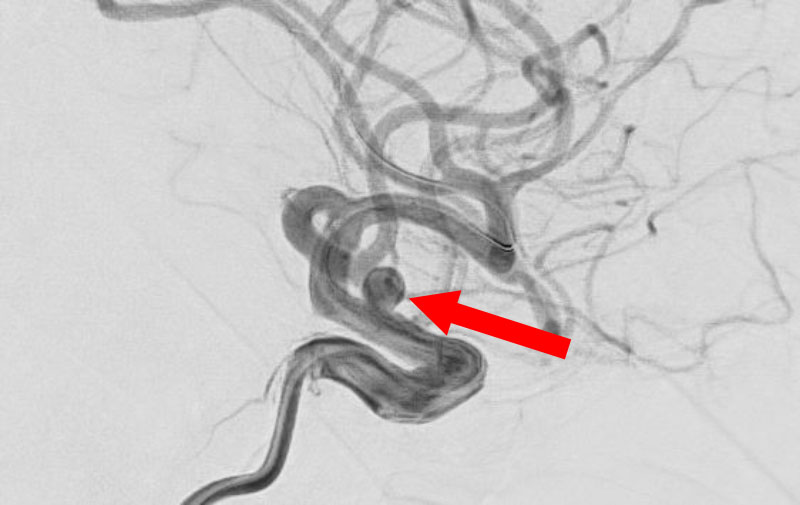

くも膜下出血

左中大脳動脈瘤破裂

40代

救急外来

No.1596 手術前